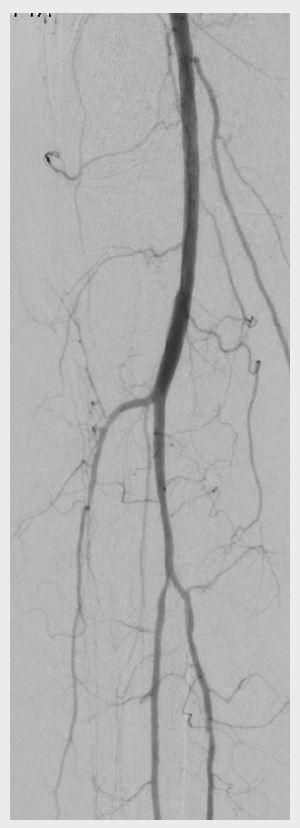

Figure 3